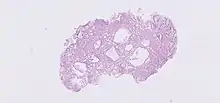

The polyps on endoscopy are usually tiny, numerous and sessile,[3] and usually scattered throughout the fundus of the stomach, where parietal cells are more numerous. They have the same colour as the gastric mucosa, and never have a stalk.[4] When the polyps are biopsied, the pathology typically shows shortened gastric pits, and both superficial and deep cystic lesions in the fundic glands, lined by all three types of cells of acid-producing mucosa: mucous, parietal and chief cells. As sometimes parietal cell hyperplasia may develop deep dilations of gland,[5] one should be really strict in the diagnosis of FGPs (i.e. the presence of deep and superficial dilations). Infrequently, the two lesions may coexist.[3] Foci of dysplasia can sometimes be seen.[4]